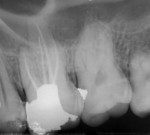

A 25-year-old male patient reported to the outpatient department with the chief complaint of pain in the left upper back region of jaw for the last 2 to 3 days. The patient also gave a history of disturbed sleep. Findings from the clinical examination revealed a deep carious lesion in the maxillary left first molar. The tooth was sensitive to percussion and elicited positive response on thermal and electric pulp testing; pain persisted even after removal of the stimulus. An intraoral periapical radiograph revealed a radiolucency approximating the pulp and periodontal ligament space widening was also present (Figure 1). On correlating the clinical and radiographic findings, a diagnosis of acute irreversible pulpitis with apical periodontitis was made and a decision to perform root canal treatment of maxillary left first molar was determined. The patient was informed about the treatment, and he provided informed consent. The patient was administered local anesthesia of 2% lidocaine containing 1:80,000 epinephrine and an access opening was performed using a rubber dam isolation. The clinical evaluation of the internal anatomy revealed 3 principal root canal systems: mesiobuccal (MB), distobuccal (DB), and palatal (P). After careful probing using a DG 16 endodontic explorer (Dentsply Sirona, dentsply.com), under 2.5X magnification using surgical loupes (Keeler Instruments, keelerusa.com), a small hemorrhagic point was noticed in a groove from the MB orifice in a palatal direction. A similar hemorrhagic point was also observed near the orifice of the main palatal canal. The conventional triangular access was modified to a trapezoidal shape to improve access to the additional canals. In both areas, there was a “catch” present with the endodontic explorer. Multiple radiographs at different angulations were not conclusive, so a multislice CBCT (Kodak, Carestream, carestreamdental.com) scan was performed of the involved tooth along with adjacent teeth. All required measures were taken to protect the patient from radiation. The images were obtained in transverse, axial, and sagittal sections of 0.5-mm thickness, which is used routinely. CBCT scan slices revealed 5 canals (2 mesiobuccal, 2 palatal, and 1 distobuccal) in the axial images at the coronal (Figure 2) and middle thirds (Figure 3). In the apical third, the palatal root had only 1 canal indicating that the 2 canals were fused between middle and apical thirds (Figure 4).